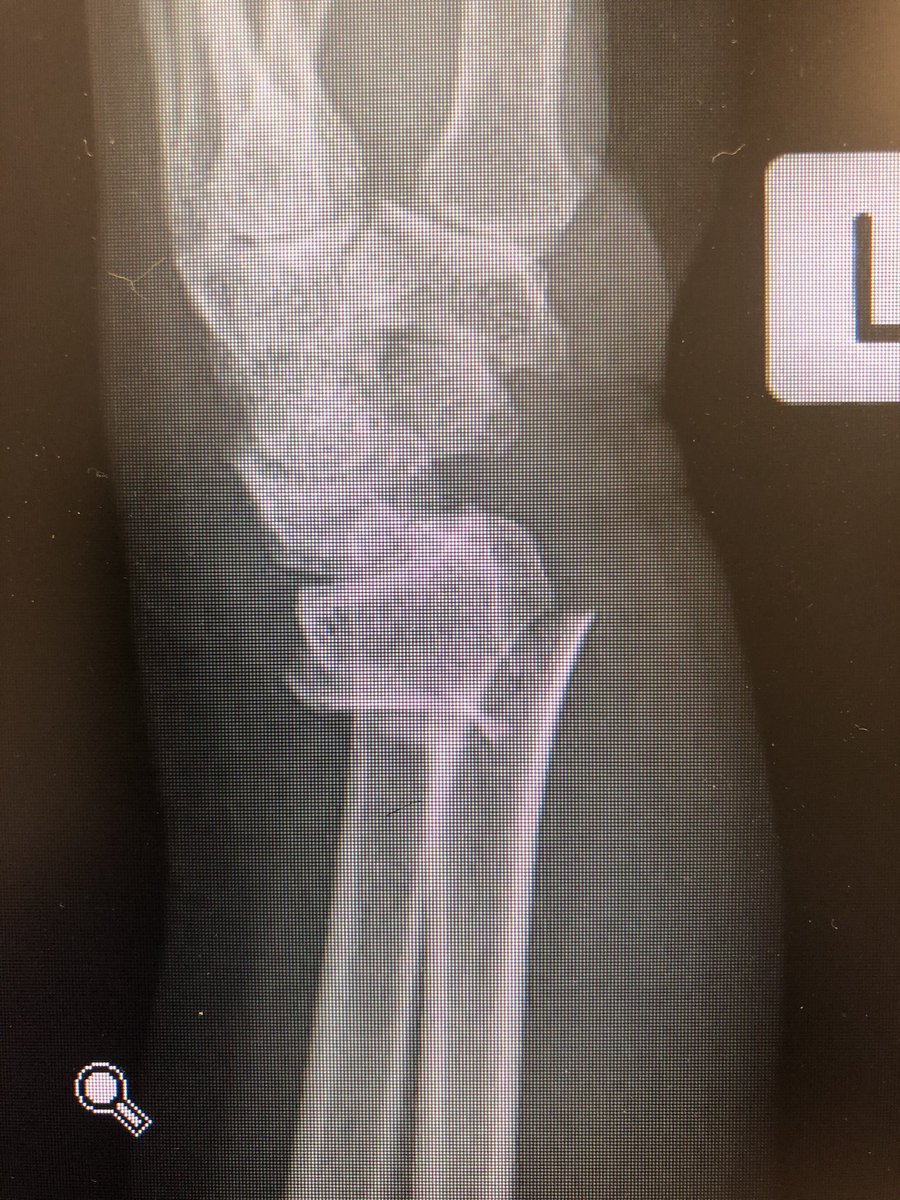

Simple everyday distal radius fracture. 60 yr old nurse. Medically well. #OrthoTwitter

I see conventionally this would be called an ‘extra-articular’ fracture.

Do we oversimplify this? Isn’t DRUJ a ‘joint’?

Isn’t the distal ulna getting all into the business of the carpals a ‘joint disruption’?

I would fix this.